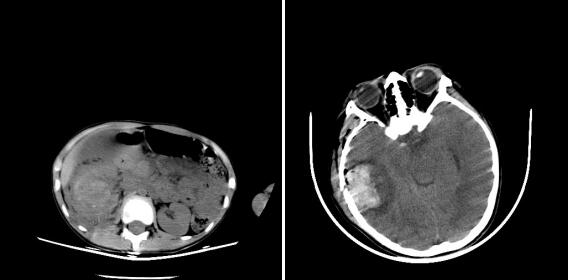

小海洋不幸遭遇车祸,就诊于我院急诊科时已出现失血性休克,烦躁,心率增快,血压下降,血红蛋白测不出,影像学提示右肾周大量积血。这是一场与时间的赛跑,在急诊抢救室会诊评估病情并与外科沟通后,我重症医学科住院总侯彦丽当即联系介入科,并向科室值班二线王春亚医师汇报情况,科室做好收治准备,做好无缝交接,避免时间的延误。

在收入重症医学科时患儿出现瞳孔不等大等脑疝表现, CT提示颅内血肿在进一步扩大、中线移位。虽已至凌晨,但介入科彭玉萍、刘强教授等人仍然毫无怨言,以最快速度赶至医院。神经外科刘重霄教授反复评估病情,患儿亟需去骨瓣减压以挽救生命。介入与神经外科手术术前准备同时进行。当迅速、准确找到出血罪犯血管并栓塞后,虽患儿的血尿颜色迅速变淡,血压趋于平稳,但大家的心仍高悬未搁。大出血后血小板、凝血因子大量消耗,凝血功能严重紊乱。进则面临术中致命性出血,退则随时因脑疝呼吸、循环骤停。输血科值班人员立即调配新鲜冰冻血浆、血小板等来给外科手术保驾。